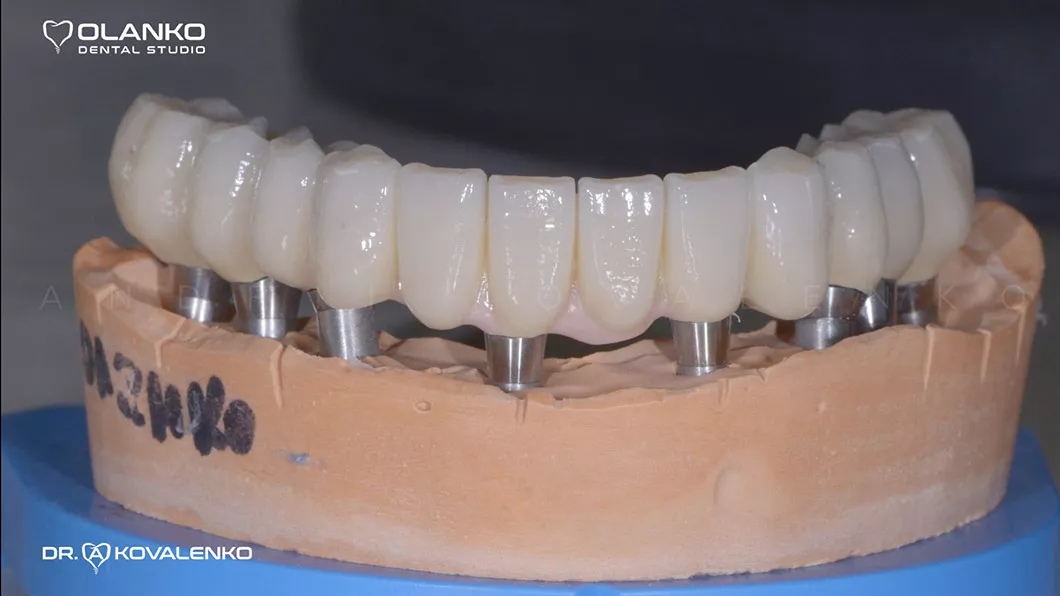

Вид готовых керамических коронок и мостовидных протезов

Клинический случай 1 имплантация зубов